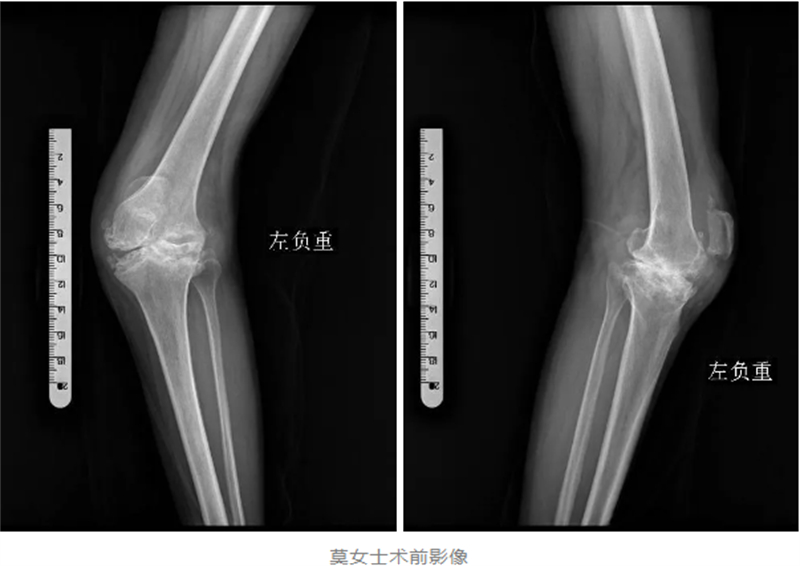

入院后,经过详细的检查,医生发现莫女士的左膝关节已经严重破坏,甚至达到了毁损的程度。韦健博士介绍,对于常规的“腿不歪”的严重膝关节磨损,用普通膝关节假体进行人工膝关节表面置换手术即可解决行走及疼痛问题,但对于莫女士这种罕见的、严重变形的毁损型膝关节,普通膝关节假体已经无法满足手术需求。

对于莫女士来说,这不仅是一次手术,更是她重获健康、重拾生活信心的关键。因此,韦健博士及其团队经过充分的讨论和周密的术前准备,决定采用髁限制型人工膝关节假体,为莫女士进行一场“美容”手术,帮助她实现重塑“大长腿”的梦想。